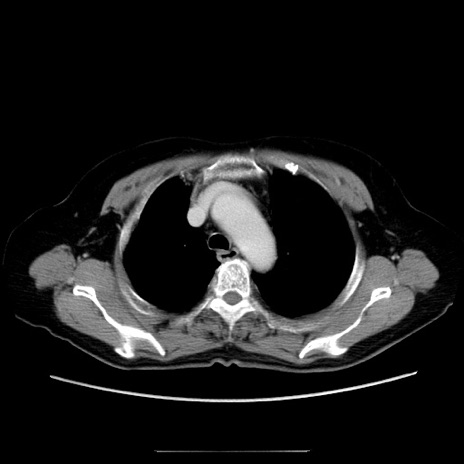

冠状断像

【症例】70歳代女性

【主訴】お腹が張る

【現病歴】1週間くらい前から腹部膨満の自覚あり。昨日夜から増悪したため、本日救急外来受診。

【身体所見】意識清明、BT 36.5℃、BP 165/106mmHg、HR 80bpm、SpO2 98%、腹部:膨満、軟、自発痛・圧痛なし、触診にて不快感あり、腸蠕動音:減弱

【データ】WBC 12600、CRP 1.04